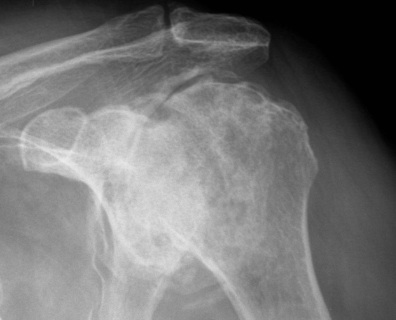

Classification / Cruess modification of Ficat-Arlet

Stage IV - significant humeral collapse with loss integrity joint surface

Stage V - degeneration extends to involve glenoid

Superior head collapse at 90° mark

- area of peak contact stress in abduction

- glenoid rarely affected